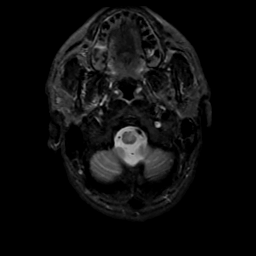

MR Study #10, April 28, 1991 -- Slice #3

[Home][Help][Clinical][Tour 1][Tour 2] Slice 3